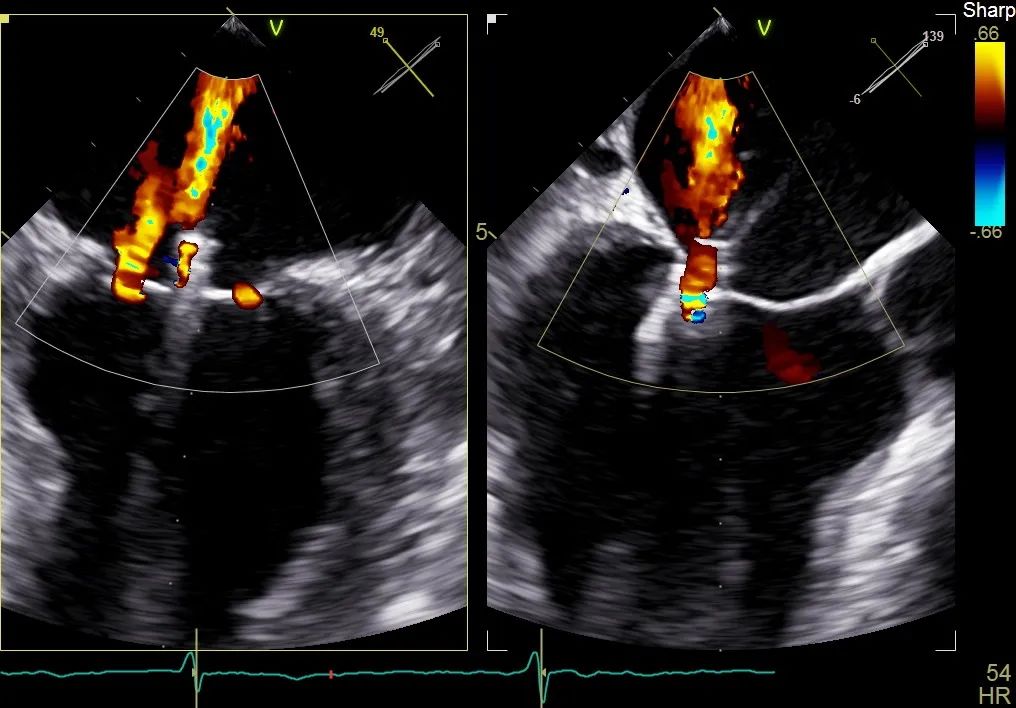

术前行经食道超声评估:继发性二尖瓣反流,反流程度4+;二尖瓣有效反流口面积(EROA) 0.81 cm²,缩流颈宽度18 mm,反流容积112.36ml,二尖瓣瓣口面积5.06 cm²,平均跨瓣压差5 mmHg,二尖瓣前叶(A2)长度15mm,二尖瓣后叶(P2)长度9 mm;左房内径54mm,左室收缩末期内径50mm,左室射血分数43%,肺动脉压83 mmHg。

术前食道超声可见二尖瓣重度反流,前后叶对合不全伴有间隙,且反流束宽度18mm